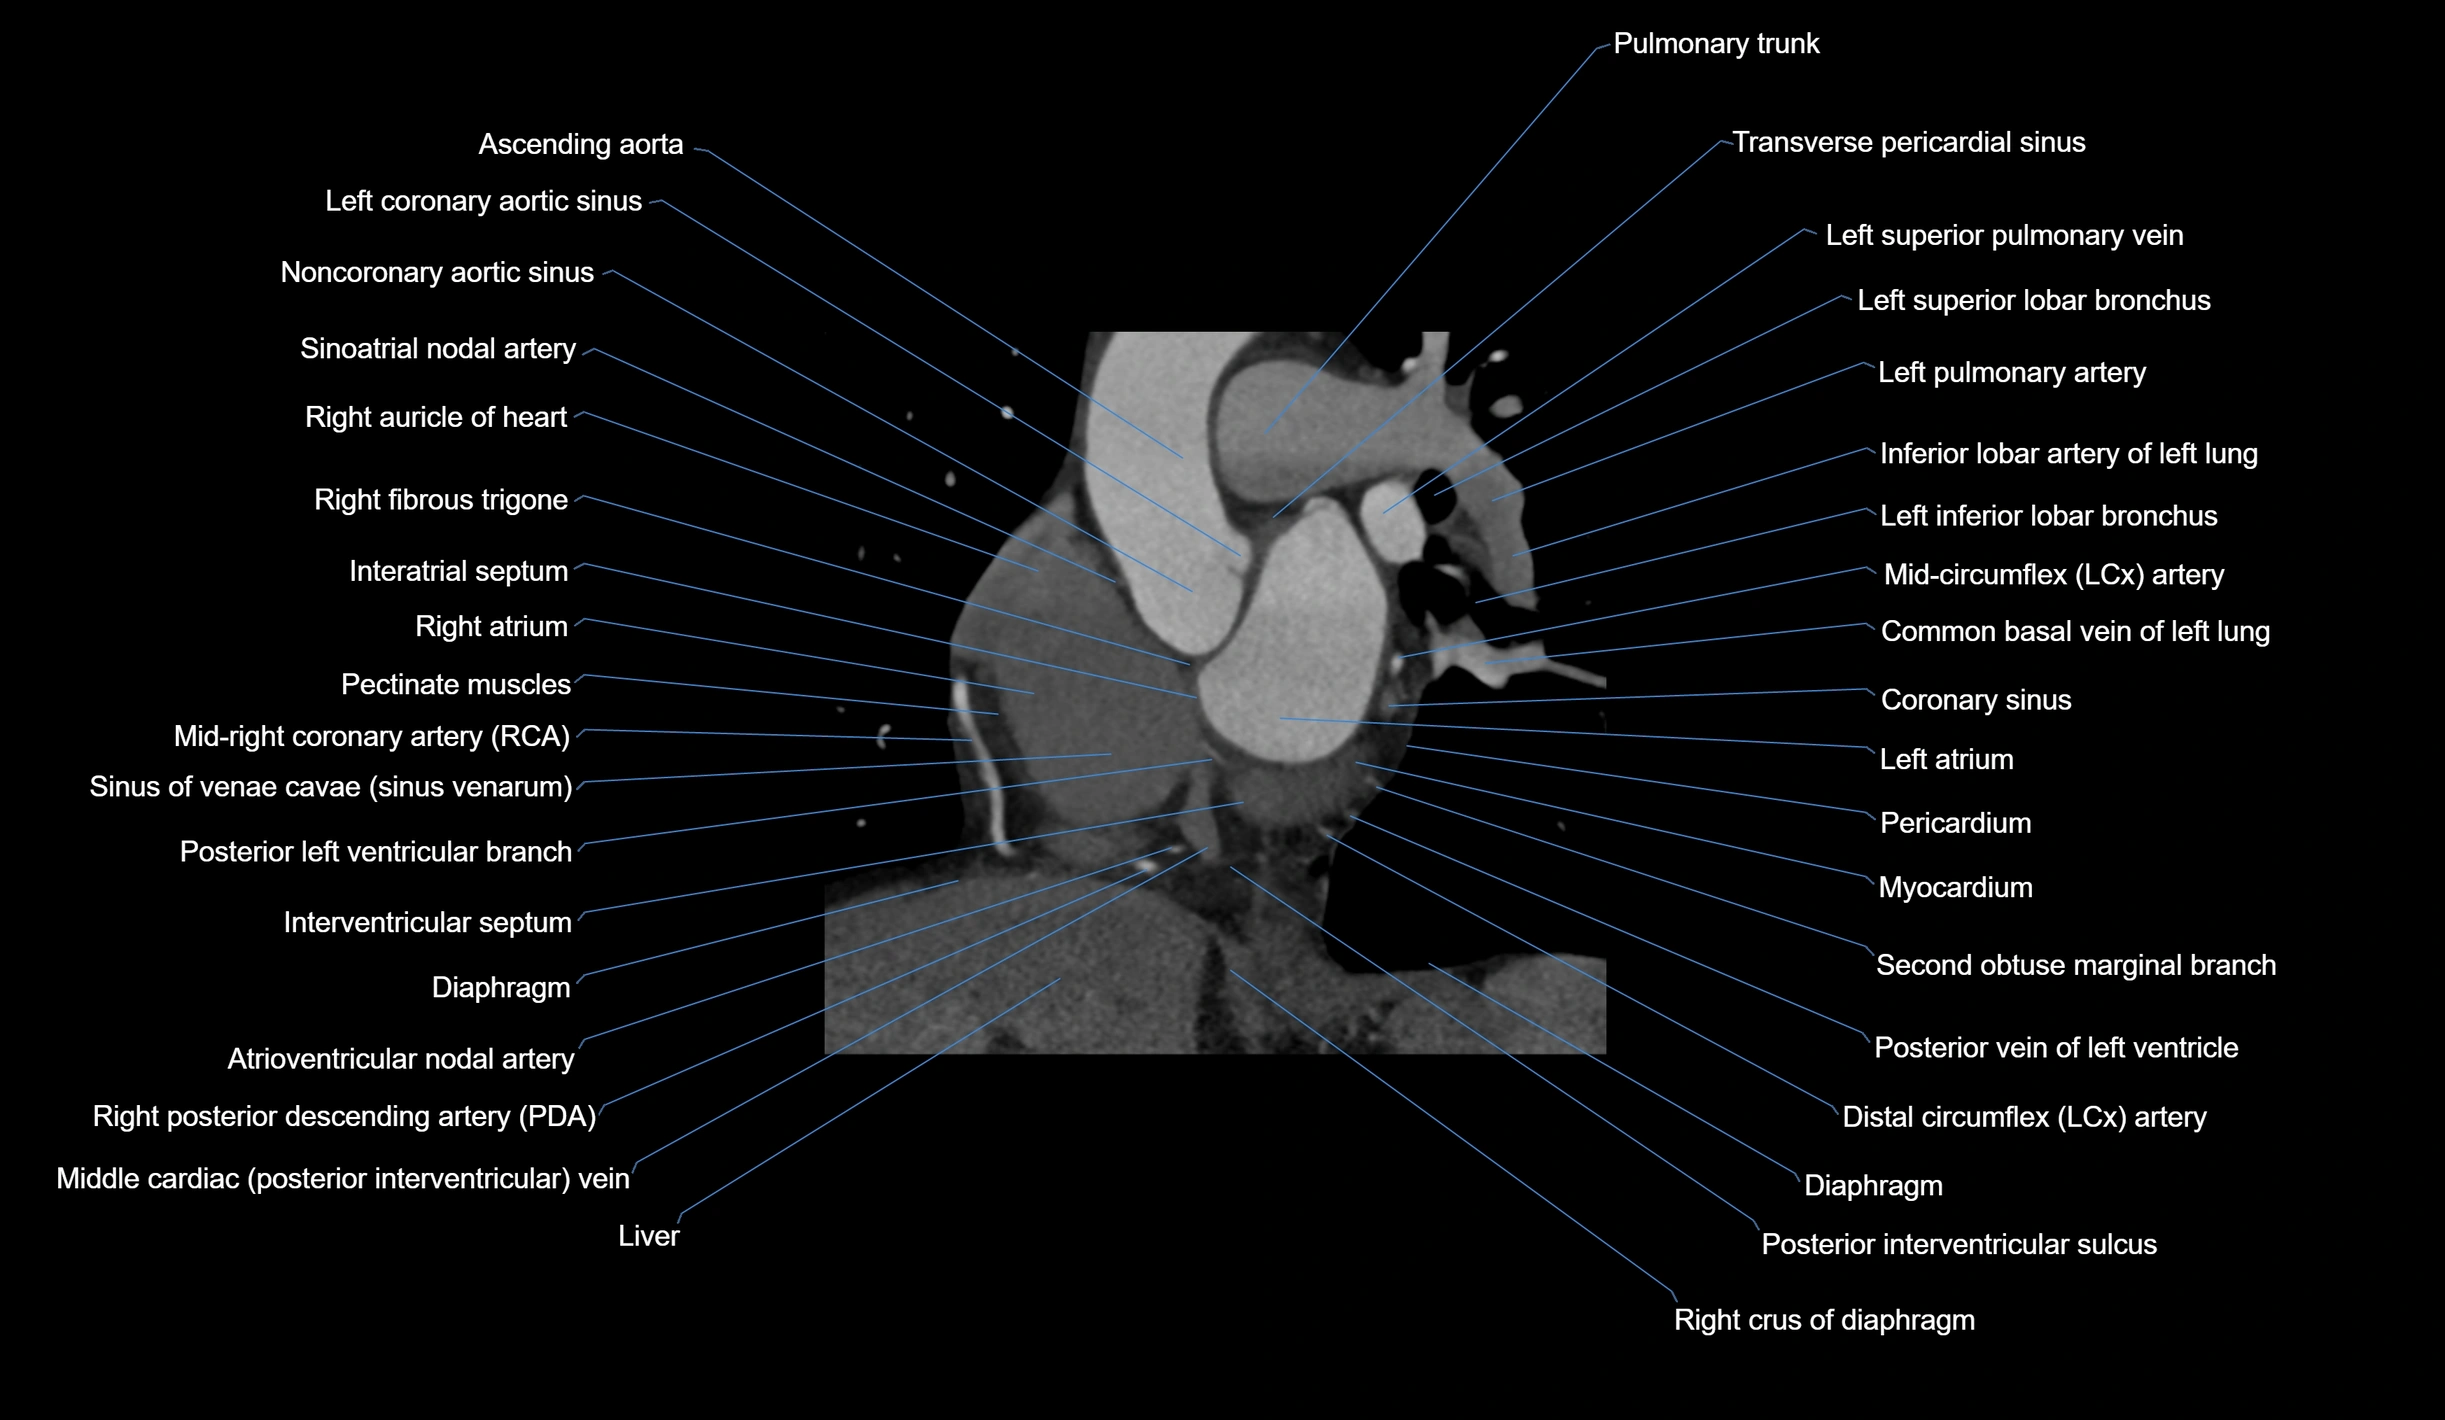

- Ascending aorta

- Coronary sinus

- Interatrial septum

- Left atrium

- Left coronary aortic sinus

- Left pulmonary artery

- Left superior lobar bronchus

- Left superior pulmonary vein

- Noncoronary aortic sinus

- Pectinate muscles

- Pericardium

- Pulmonary trunk

- Right atrium

- Right auricle of heart

- Right crus of diaphragm

- Right fibrous trigone

- Right posterior descending coronary artery (Right PDA)

- Sinoatrial nodal artery

- Sinus of venae cavae (sinus venarum)

- Transverse pericardial sinus